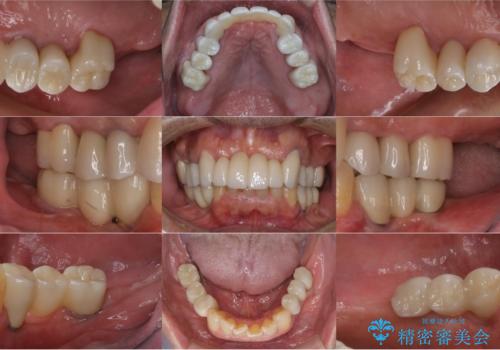

孫から口臭を指摘され来院、全顎治療で噛み合わせ、見た目、口臭全て劇的改善!

まずは歯周病の治療と抜くしかない歯を抜き、インプラント治療とセラミック治療を行いました。

治療中でも見た目が問題ない様に仮歯を製作していきますが、今回は奥歯に仮歯を入れることが不可能であったため、インプラントが使用できるまでの半年間は入れ歯を使用して頂きました。